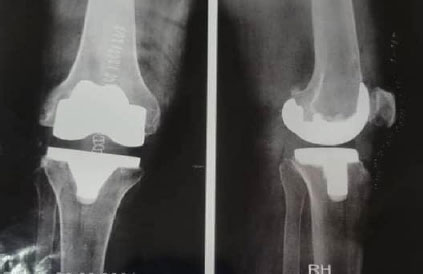

All patients exhibited advanced disease corresponding to stages IV or V (Fig. 2a,b). The full-length standing radiograph was performed in only three patients. The mean HKA angle was 171.35° ± 10°, indicating a mild global varus alignment of the mechanical axis of the lower limb.

Bilateral anteroposterior ( a ) and lateral ( b ) weight-bearing radiographs of the knees showing bilateral medial compartment osteoarthritis, more pronounced in the left knee associated with varus deformity, stage IV and V according to Ahlbäck.